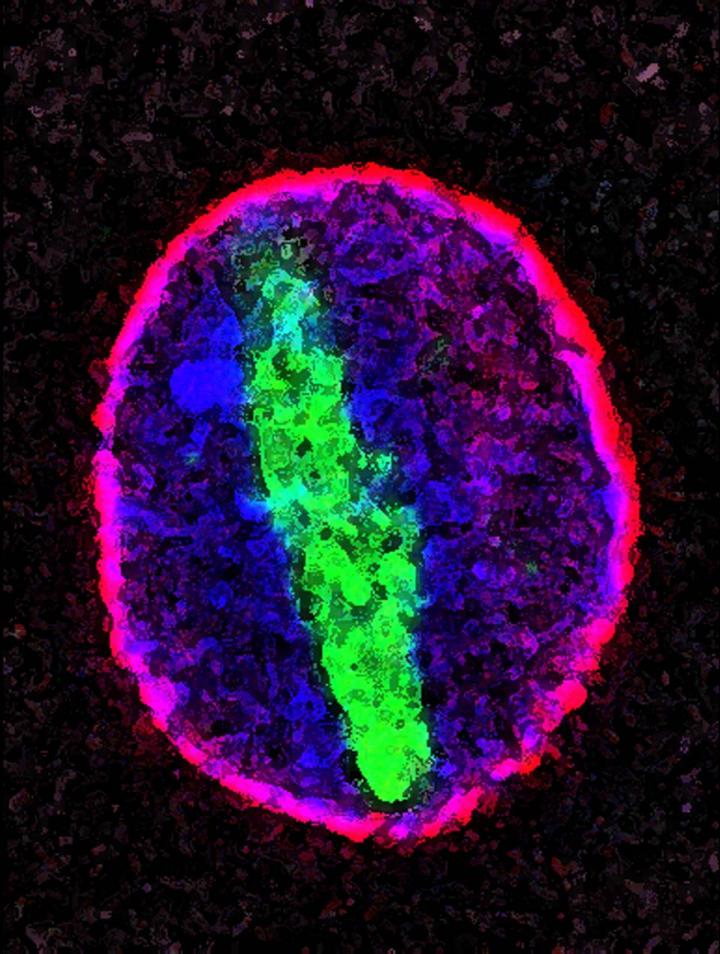

A genetic mutation implicated in ALS and FTD prevents proteins (green) from entering and exiting the cell's nucleus (pink).

Photo courtesy of NIGMS. Source: Maximiliano D'Angelo and Martin Hetzer, Salk Institute